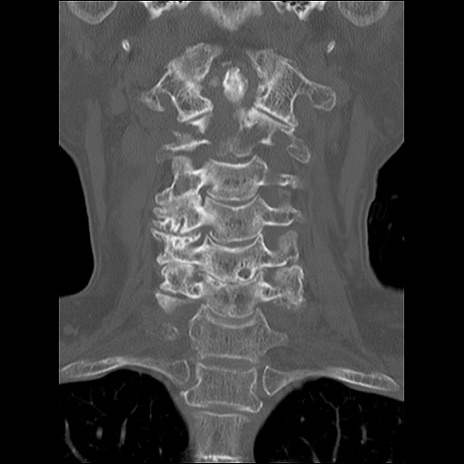

症例48 頚椎CT(冠状断像)

異常所見と診断は?

頚椎CT